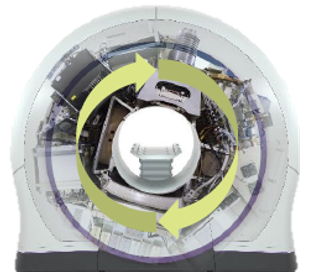

ラディザクト(Radixact)は、アキュレイ社が開発した最新の放射線治療装置で、トモセラピー技術の進化形として高精度かつ柔軟な治療を実現。

360度回転しながららせん状に照射することが可能で、複雑な形状や広範囲にわたる腫瘍にも均一かつ集中的な照射が可能。さらに、内蔵された高精度のCTにより、毎回の治療前に腫瘍の位置を正確に確認し、ズレを補正する画像誘導放射線治療(IGRT)を実施し、照射の精度を常に維持します。精密さと効率性を兼ね備えたラディザクトは、現代のがん治療において極めて有効な装置です。

360度回転しながららせん状に照射することが可能で、複雑な形状や広範囲にわたる腫瘍にも均一かつ集中的な照射が可能。さらに、内蔵された高精度のCTにより、毎回の治療前に腫瘍の位置を正確に確認し、ズレを補正する画像誘導放射線治療(IGRT)を実施し、照射の精度を常に維持します。精密さと効率性を兼ね備えたラディザクトは、現代のがん治療において極めて有効な装置です。

360度回転をしながら行う照射とバイナリマルチリーフコリメータ(MLC)

バイナリMLCといった独自のシステムを搭載し、従来のMLCの50倍以上の速さで開閉が可能。放射線を照射・遮断する動作をミリ秒単位で制御し、複雑な腫瘍の形状にも細かく対応が可能で、照射線量を精密に調整が行えます。360度回転しながら行う照射と組み合わせることで、複雑な形状の腫瘍や複数の腫瘍にも的確に照射ができ、正常組織への影響を最小限に抑えながら高精度な治療が実現します。